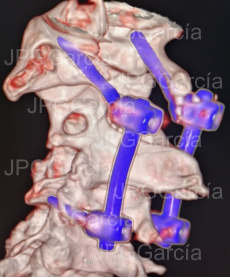

ESTUDIO DE CONTROL TOMOGRÁFICO CON COLOCACIÓN DE TORNILLOS Y BARRAS AL ATLAS Y AXIS